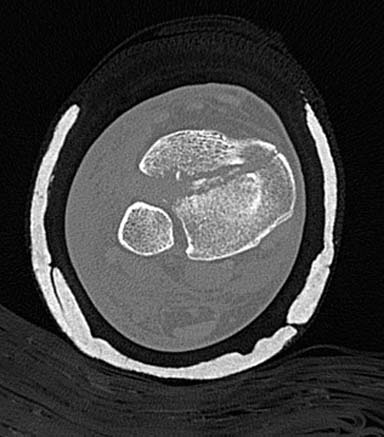

Первый случай, где перелом в результате падения с небольшой высоты, где мортиз рентген снимок показал отстутствие укорочения наружной

лодыжки и КТ срезы подсказали направления атаки. После такой фиксации нет надобности в гипсовой повязке, брейс и через две недели движения в

суставе без нагрузки.